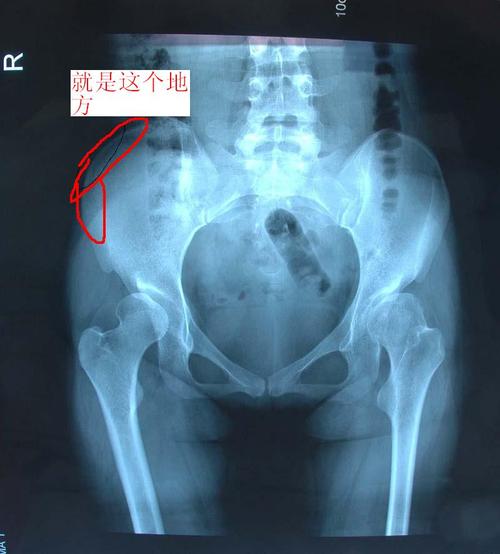

几个月前在学校运动会上跑完一百米后,大腿外侧上面接近腰部的骨头就

骶(di)骨:从背后沿着脊椎一直往下摸,腰部以下微微凸起的地方是骶骨

骶骨痛

髂骨在哪?

髂骨疼

髂骨突出